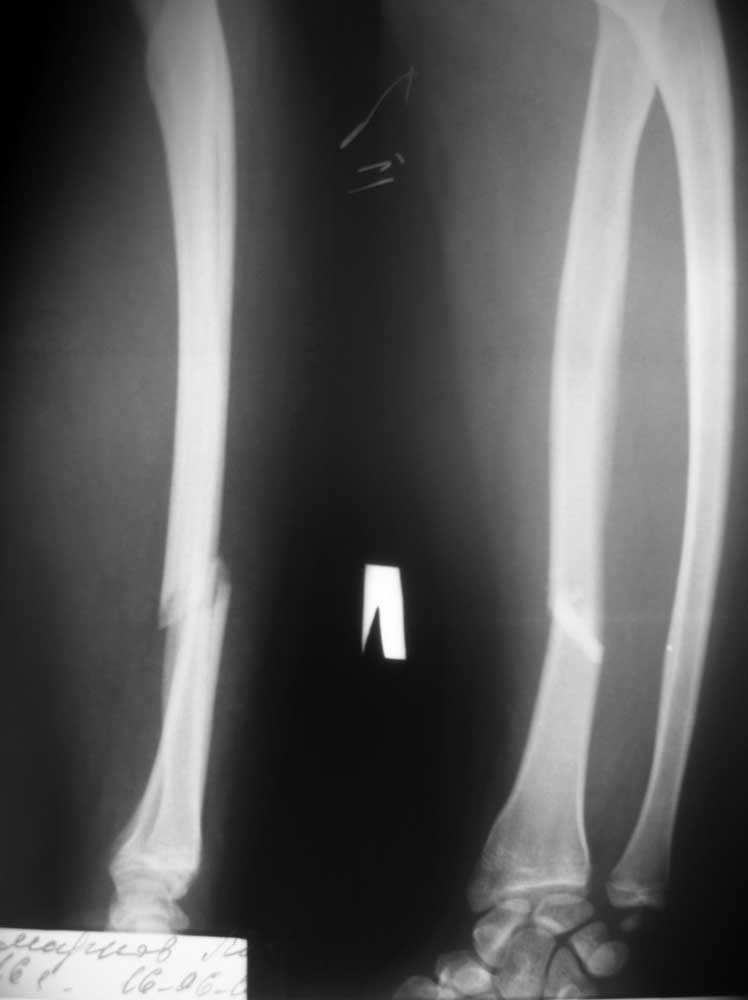

[Ortho] Перелом костей предплечья

Пострадавший, 16 лет, поступил в отделение 16.06.12. Травма в результате ДТП- воткнулся на

скутере в неподвижный автомобиль. Других повреждений нет. За прошедшие выходные какими-то

находятся под влиянием слов профессора. Считаю, что такое повреждение просто необходимо

оперировать, но чтобы переубедить пострадавшего, необходимо авторитетное мнение

уважаемого сообщества. PS. Если операция, то может быть есть какие-то особенности. Заранее

благодарен всем, высказавшим свое мнение. Любое!